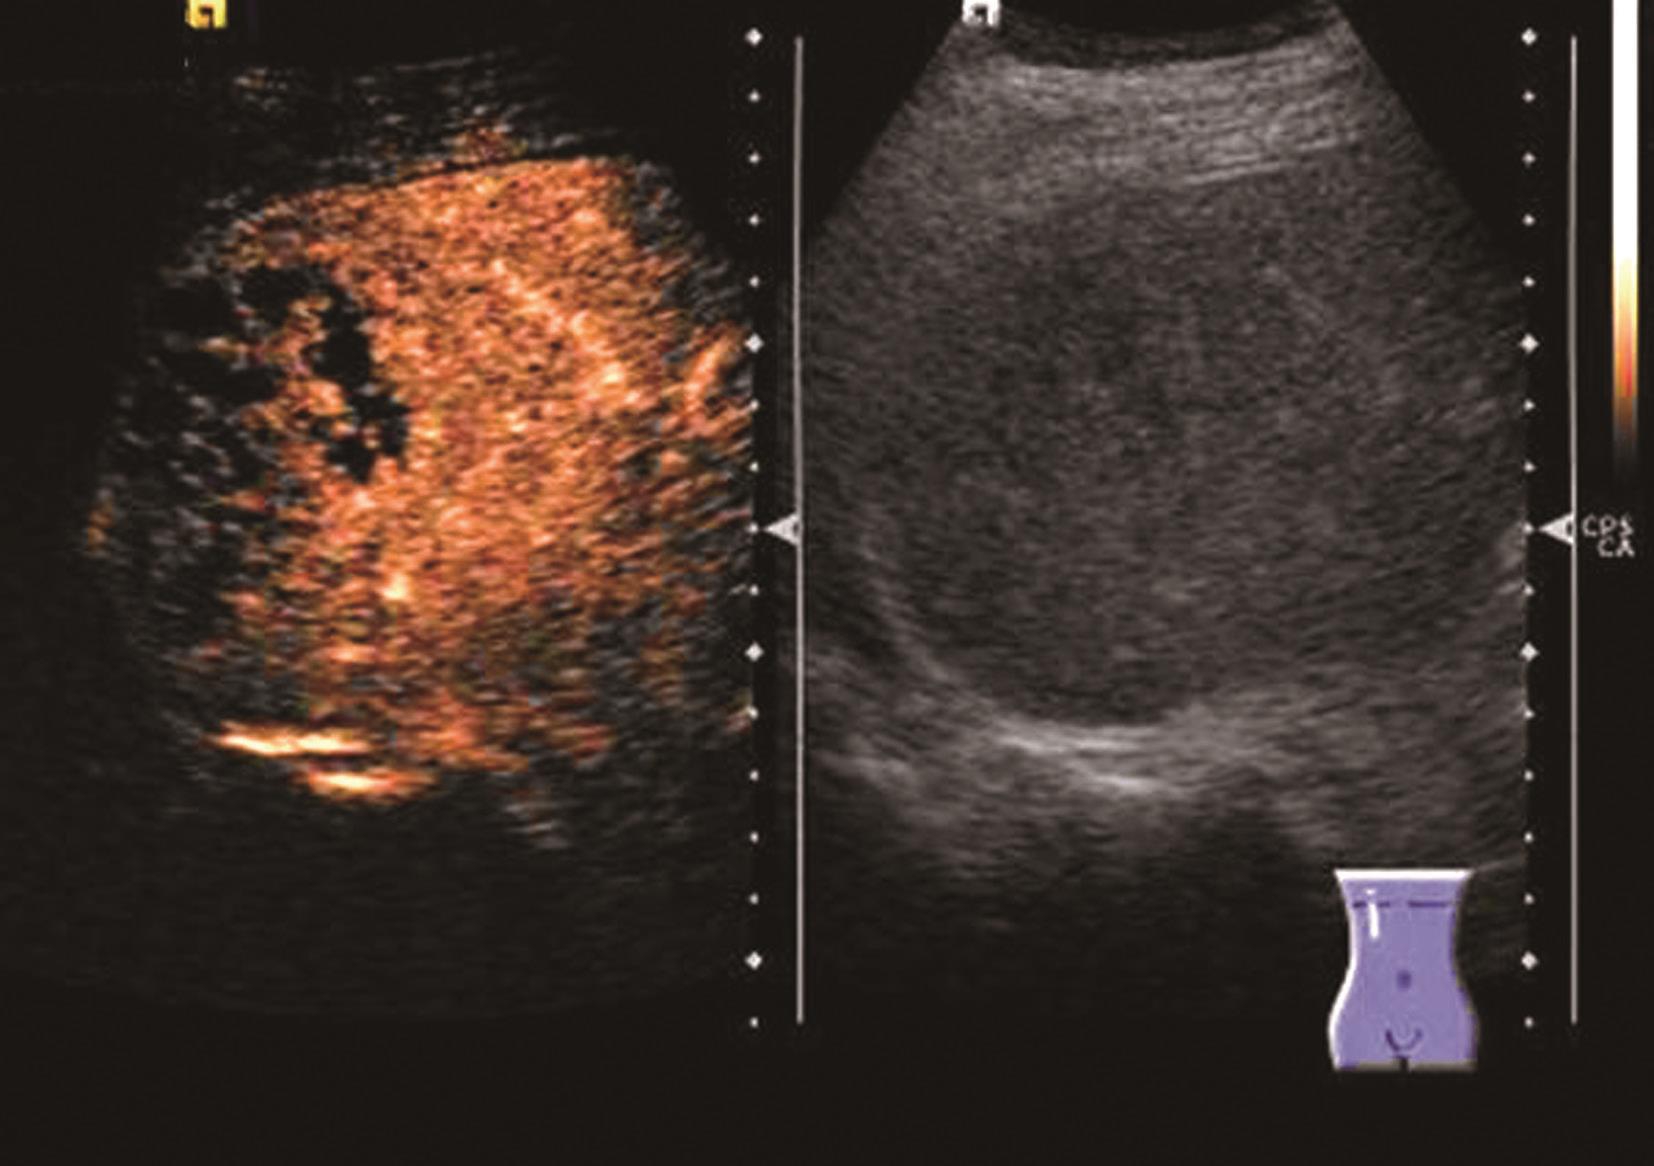

(2)彩色多普勒超声:

尽管血管瘤内血管丰富,但血流速度极为缓慢,彩色多普勒可显示部分血管瘤内部或周边的斑状或短线状血管,频谱均为低速血流。对小血管瘤,尤其位于肝脏深部者则难以检测到血流信号。

(3)超声造影表现:

血管瘤典型的超声造影表现为:动脉相周边结节样或环状高回声增强,门静脉相和延迟相造影剂进行性向心性填充,填充可以是完全性的或部分性,60%~80%的肝血管瘤表现为这一典型特征。造影剂填充的速度根据血管瘤的大小而不同,小血管瘤只需1min,大的可能需要10min。20%~30%肝血管瘤内含有丰富的动静脉短路,充填时间会减短到1min甚至几秒,因此造影后的60秒内观察肝血管瘤的增强特征是非常重要的。如果瘤内有纤维化或栓塞,造影剂填充不完全,这种情况也可能发生在较小的血管瘤。如果有典型的造影增强行为可以诊断血管瘤,而不需进一步其他影像检查。肝血管瘤超声造影动脉期、静脉期及延迟期超声声像图表现如图5-21-13~图5-21-15所示。